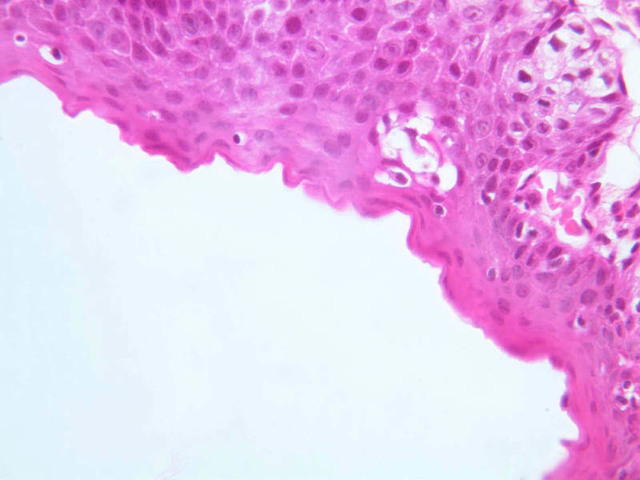

Using the low or medium power objective, scan the section of the rectoanal junction on slide B-26 (H&E [2.5x-labeled, 10x-labeled] [2.5x, 20x, 40x] [2.5x, 20x-labeled, 40x] [20x, 40x] [20x, 40x] [20x] [2.5x, 10x, 20x, 40x]) . Proximally, the rectal mucosa exhibits crypts of Lieberk\xFChn and the simple columnar epithelium is exceptionally rich in goblet cells. As you trace the epithelium towards the anus, you will find that the crypts disappear, then the simple columnar epithelium gives way to stratified squamous epithelium, often with a narrow intervening swath of stratified cuboidal or stratified columnar epithelium. Just proximal to the anal orifice keratin appears and just distal to the anal orifice you may be able to find sweat glands, sebaceous glands and hair follicles.